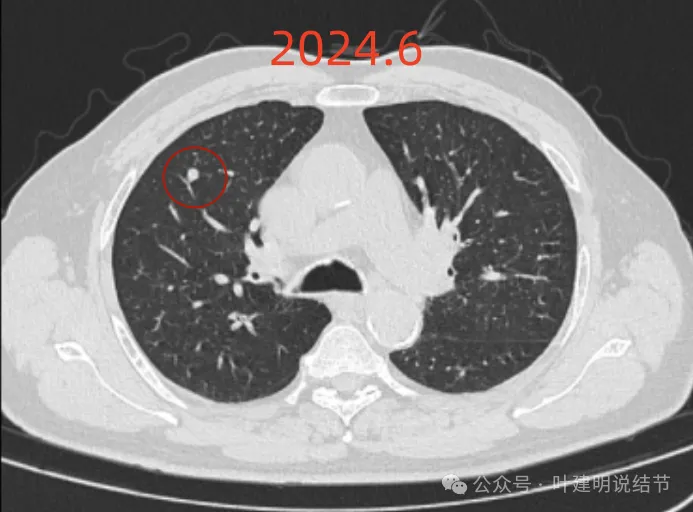

再看2024年6月时的影像:

右上没有明显变化,仍考虑良性可能性大。

左下也考虑良性,与2022年无明显变化。

右下新增病灶,混合密度,整体轮廓较清,瘤肺边界欠清。

有小血管进入,边缘毛糙。

局部有毛刺,但不够锐利;病灶感觉有一层晕似的,邻近胸膜下也有淡磨玻璃影。

实性密度为主,周围少许很淡的磨玻璃影。

边缘不平有毛刺,但不锐利;贴着胸膜但无明显牵拉。局部表面有浅分叶似的,但总体膨胀感不够。

病灶表面不光滑,边上有晕,邻近有淡磨,贴着胸膜无牵拉。

病灶边缘欠清晰,瘤肺边界稍模糊。较宽的基底贴着胸膜。

病灶有血管进入,有浅分叶,实性为主,邻近胸膜有片状淡磨玻璃影,近胸膜无牵拉。但有一定膨胀性。

病灶实性,与血管关系较为密切。

血管走向病灶,但似乎没有被病灶影响,有向内侧的分支甚至没有哪怕一点凹向病灶侧。整体显得偏模糊。

边缘区域杂乱,边糊。

这是冠状位、矢状位与轴位的影像。

增强纵隔窗见病灶内部的密度好像低于周围区域,像坏死。

邻近胸膜无牵拉,灶内有低密度区,局部有点状液性密度。邻近胸膜较为广泛的增厚或胸膜反应。

病灶与胸膜接触面宽,病灶内部密度较低。

你的结节,对比各次的影像,原来的肺多发结节主要病灶是右上叶与左下叶这两处,其他过小。直到2022年8月,右下这处均不明显的。2023年没查,今年突然发现。首先几点:1、原有的结节没有明显进展,实性且小,考虑是良性的;2、右下结节原来没有,这次检出是新发的;3、两肺多发结节必不是右下这处新检出的病灶转移的(因为它们原来就有,右下这处是新发的)。右下这处的特点则有以下几点:1、病灶实性密度,磨玻璃成分不明显,但总体上并不是具有强收缩力或显著膨胀性的,与恶性程度很高的肺癌似乎不符合;2、表面不平毛糙,但毛刺样征并不锐利,紧邻胸膜也无明显胸膜牵拉凹陷,不是典型恶性的影像表现;3、口服消炎无好转,不像普通急性炎症;4、纵隔窗上见病灶内部密度低,周围的密度高些,中间更像坏死或液性密度。但这么小的肿瘤容易中间缺血性坏死吗?显然这与肿瘤恶性程度高而中间乏血供而坏死是不符合的。而这种表现与肉芽肿性炎伴坏死比较符合;5、病灶与胸膜紧邻,胸膜侧在纵隔窗上见基较宽并有胸膜增厚,这与炎性改变更为符合。我的感觉总体上倾向肉芽肿性炎可能性大,建议完善结核与隐球菌方面检查,并同时CT引导下穿刺活检(这个位置穿刺容易也风险小,又能取得病灶依据)。若有结核或隐球菌方面阳性结果,请内科医生按相应结果治疗;若均阴性,且穿刺也未见癌细胞,则可考虑3个月左右复查随访,当然也可直接局部胸腔镜下局部切了化验,既达诊断目的,也去除病灶。这要你自己酌情考虑选择。意见供参考!